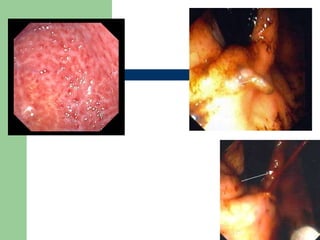

Gastritis Dieulafoy’s lesion

Dieulafoy’s vascular  malformations   Dilated Arterial Lesions